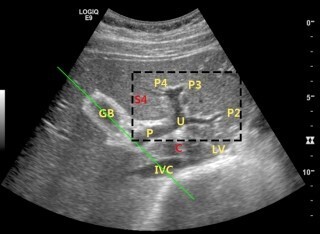

Rt. subcostal - ③ 간정맥의 늑간하스캔 (hepatic v.이 IVC로 모이는 삼지창 모양) ④ 좌우간문맥 분지의 횡스캔 (정밀)

portal vein branch가 H 모양으로 보이도록. "Recumbent H"